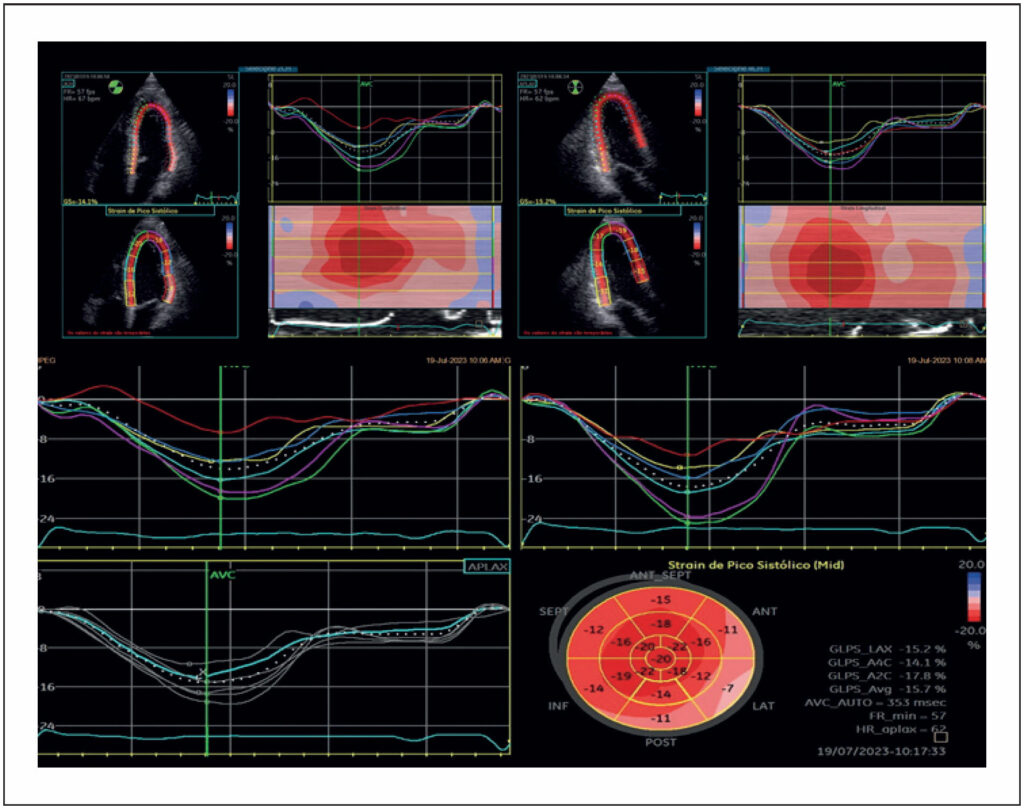

Role of Strain Echocardiography in the Evaluation of Patients with Chagas Disease

Chagas disease continues to be a significant public health challenge, affecting approximately six million people worldwide. With increasing globalization, Trypanosoma cruzi has already been detected in regions that were not previously considered endemic for the transmission vector, thus becoming one of the main neglected parasites. Although a percentage of infected individuals remain asymptomatic in the chronic indeterminate form of the disease, it is estimated that 2% to 3% of all patients annually progress to the cardiac form. Chagas heart disease was the most severe manifestation of Chagas disease, clinically appearing with heart failure, ventricular and supraventricular arrhythmias, conduction disorders, and embolic events.

The echocardiogram is an important propaedeutic method in the evaluation of patients with Chagas disease, especially in the presence of Chagas heart disease. In general, the echocardiogram investigates parameters related to the analysis of segmental contractility and global systolic function, which is essential for the treatment and prognosis of the disease. However, even well-established variables in the literature, such as ejection fraction, face challenges in simulating all the pathological aspects of Chagas disease.